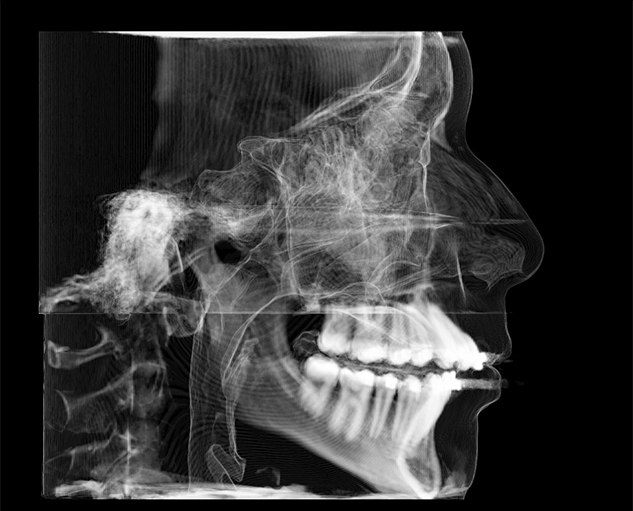

Teleradiology is an internet based radiology system wherein captured images from sources like X-Ray, CT Scan, CBCT Scan, MRI etc are sent to another location via web,so that an expert radiologist at another location can read the images for the purpose of generating reports and image portfolios.

On every case submitted, we ask you to identify the clinical purpose(s). Radreaders has developed specific diagnostic objectives for each clinical purpose that will be addressed by the radiologist. This ensures that the report is relevant to your diagnosis and treatment planning.

Click on the links below to view sample reports for some commonly indicated clinical purposes:

Cephalometric